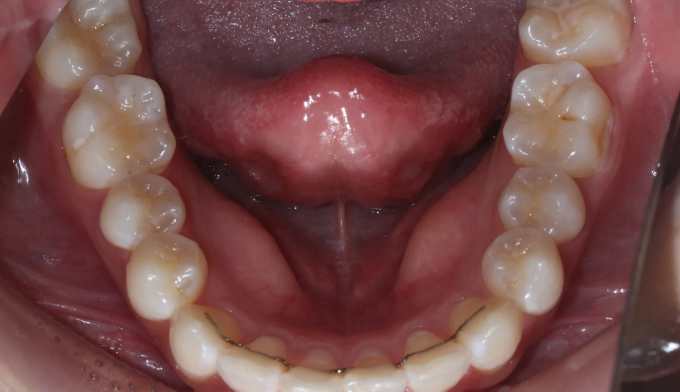

약 1년 뒤, 사랑니가 어금니 자리를 멀쩡하게 대체할 수 있게 잘 올라와주었습니다,

이제는 가지런하지 않은 앞니와 살짝 돌아간 사랑니를 가지런하게 배열해주는 일을 해야 합니다.